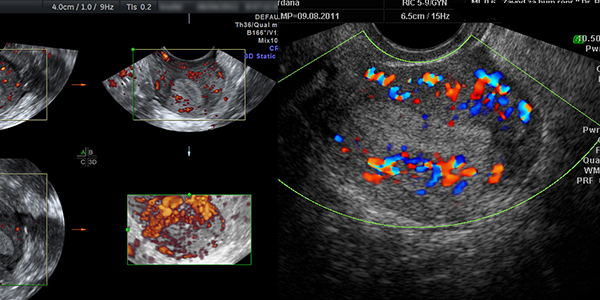

Kolor dopler ultrazvučni pregled (CD, PWD i pulsirajući dopler)

Ovaj ultrazvučni pregled podrazumijeva pregled prokrvljenosti genitalnih organa i male karlice pri čemu se ocjenjuje raspored krvnih sudova, te u njima mjeri otpor i brzina. S obzirom da se kretanje tečnosti u krvnim sudovima vidi u boji neki nazivaju ovaj pregled i ULTRAZVUK U BOJI.

Ova vrsta ultrazvučnih pregleda od posebnog je značaja kod mioma materice i cisti na jajnicima s obzirom da je to jedan od načina pouzdane procjene o mogućnosti rasta pomenutih tumora ali i otklanjanje ili potvrđivanje sumnje da se radi o malignom tumoru. Ovi pregledi traju duže, i do 30 minuta a mogu se obavljati vaginalnim putem ili preko stomaka (abdominalno).

Ova vrsta ultrazvučnog pregleda je od posebne važnosti kod krvarenja u malim trudnoćama jer pouzdano i brzo može dati ocjenu o vitalnosti ploda od koje zavisi prognoza.